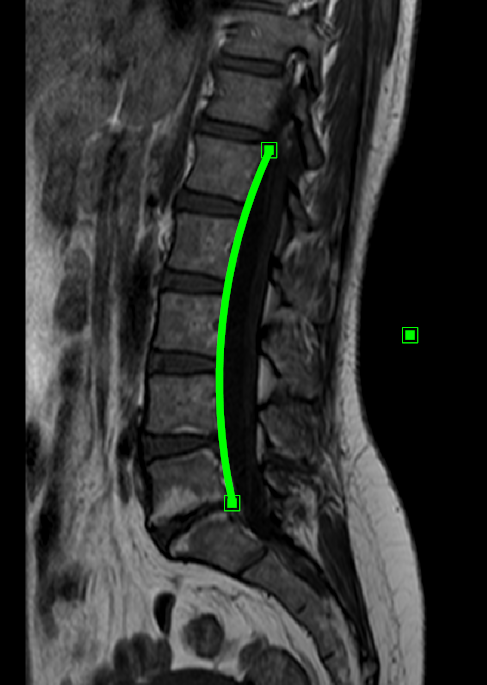

9.5.9. Lumber Curve Tool

The lumbar curve tool is used to draw a curve between two points based on the radius of a circle including those points. Follow the instructions below to use this tool:

A curve will be drawn based on the radius of a circle including those points (default radius is 22cm):